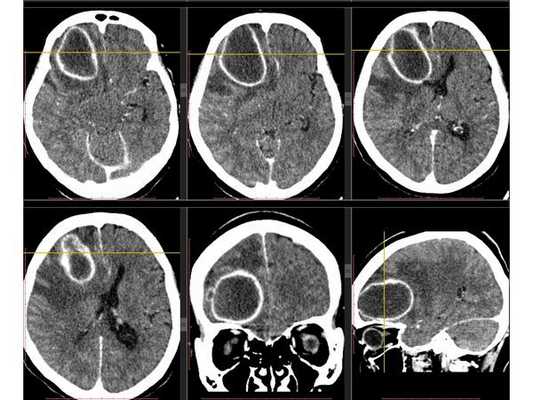

Рентгенография лёгких: без патологии. УЗИ органов брюшной полости: выявлены хронический холецистит, хронический панкреатит, диффузные изменения печени и поджелудочной железы. ЭКГ: в норме. На КТ головного мозга визуализировалось объёмное образование в правой лобной доли. Это вызвало подозрение на абсцесс, но отсутствие уровня жидкости, лихорадки и менингеального синдрома у пациентки в большей степени склонило клиническую мысль в сторону онкологического поражения. В связи с этим пациентку госпитализировали в отделении неврологии. Однако при осмотре онкологом и гинекологом данных, которые бы подтверждали наличие онкологии головного мозга, обнаружено не было. В качестве дообследования проведена КТ головного мозга с контрастным усилением. Она выявила объёмное образование в правой лобной доли с чётко очерченной капсулой. Рядом с образованием располагался отёк, срединные структуры были смещены влево примерно на 5 мм.

3D-реконструкция объёмного образования правой лобной доли головного мозга, выполненная на основании сканов КТ с контрастным усилением